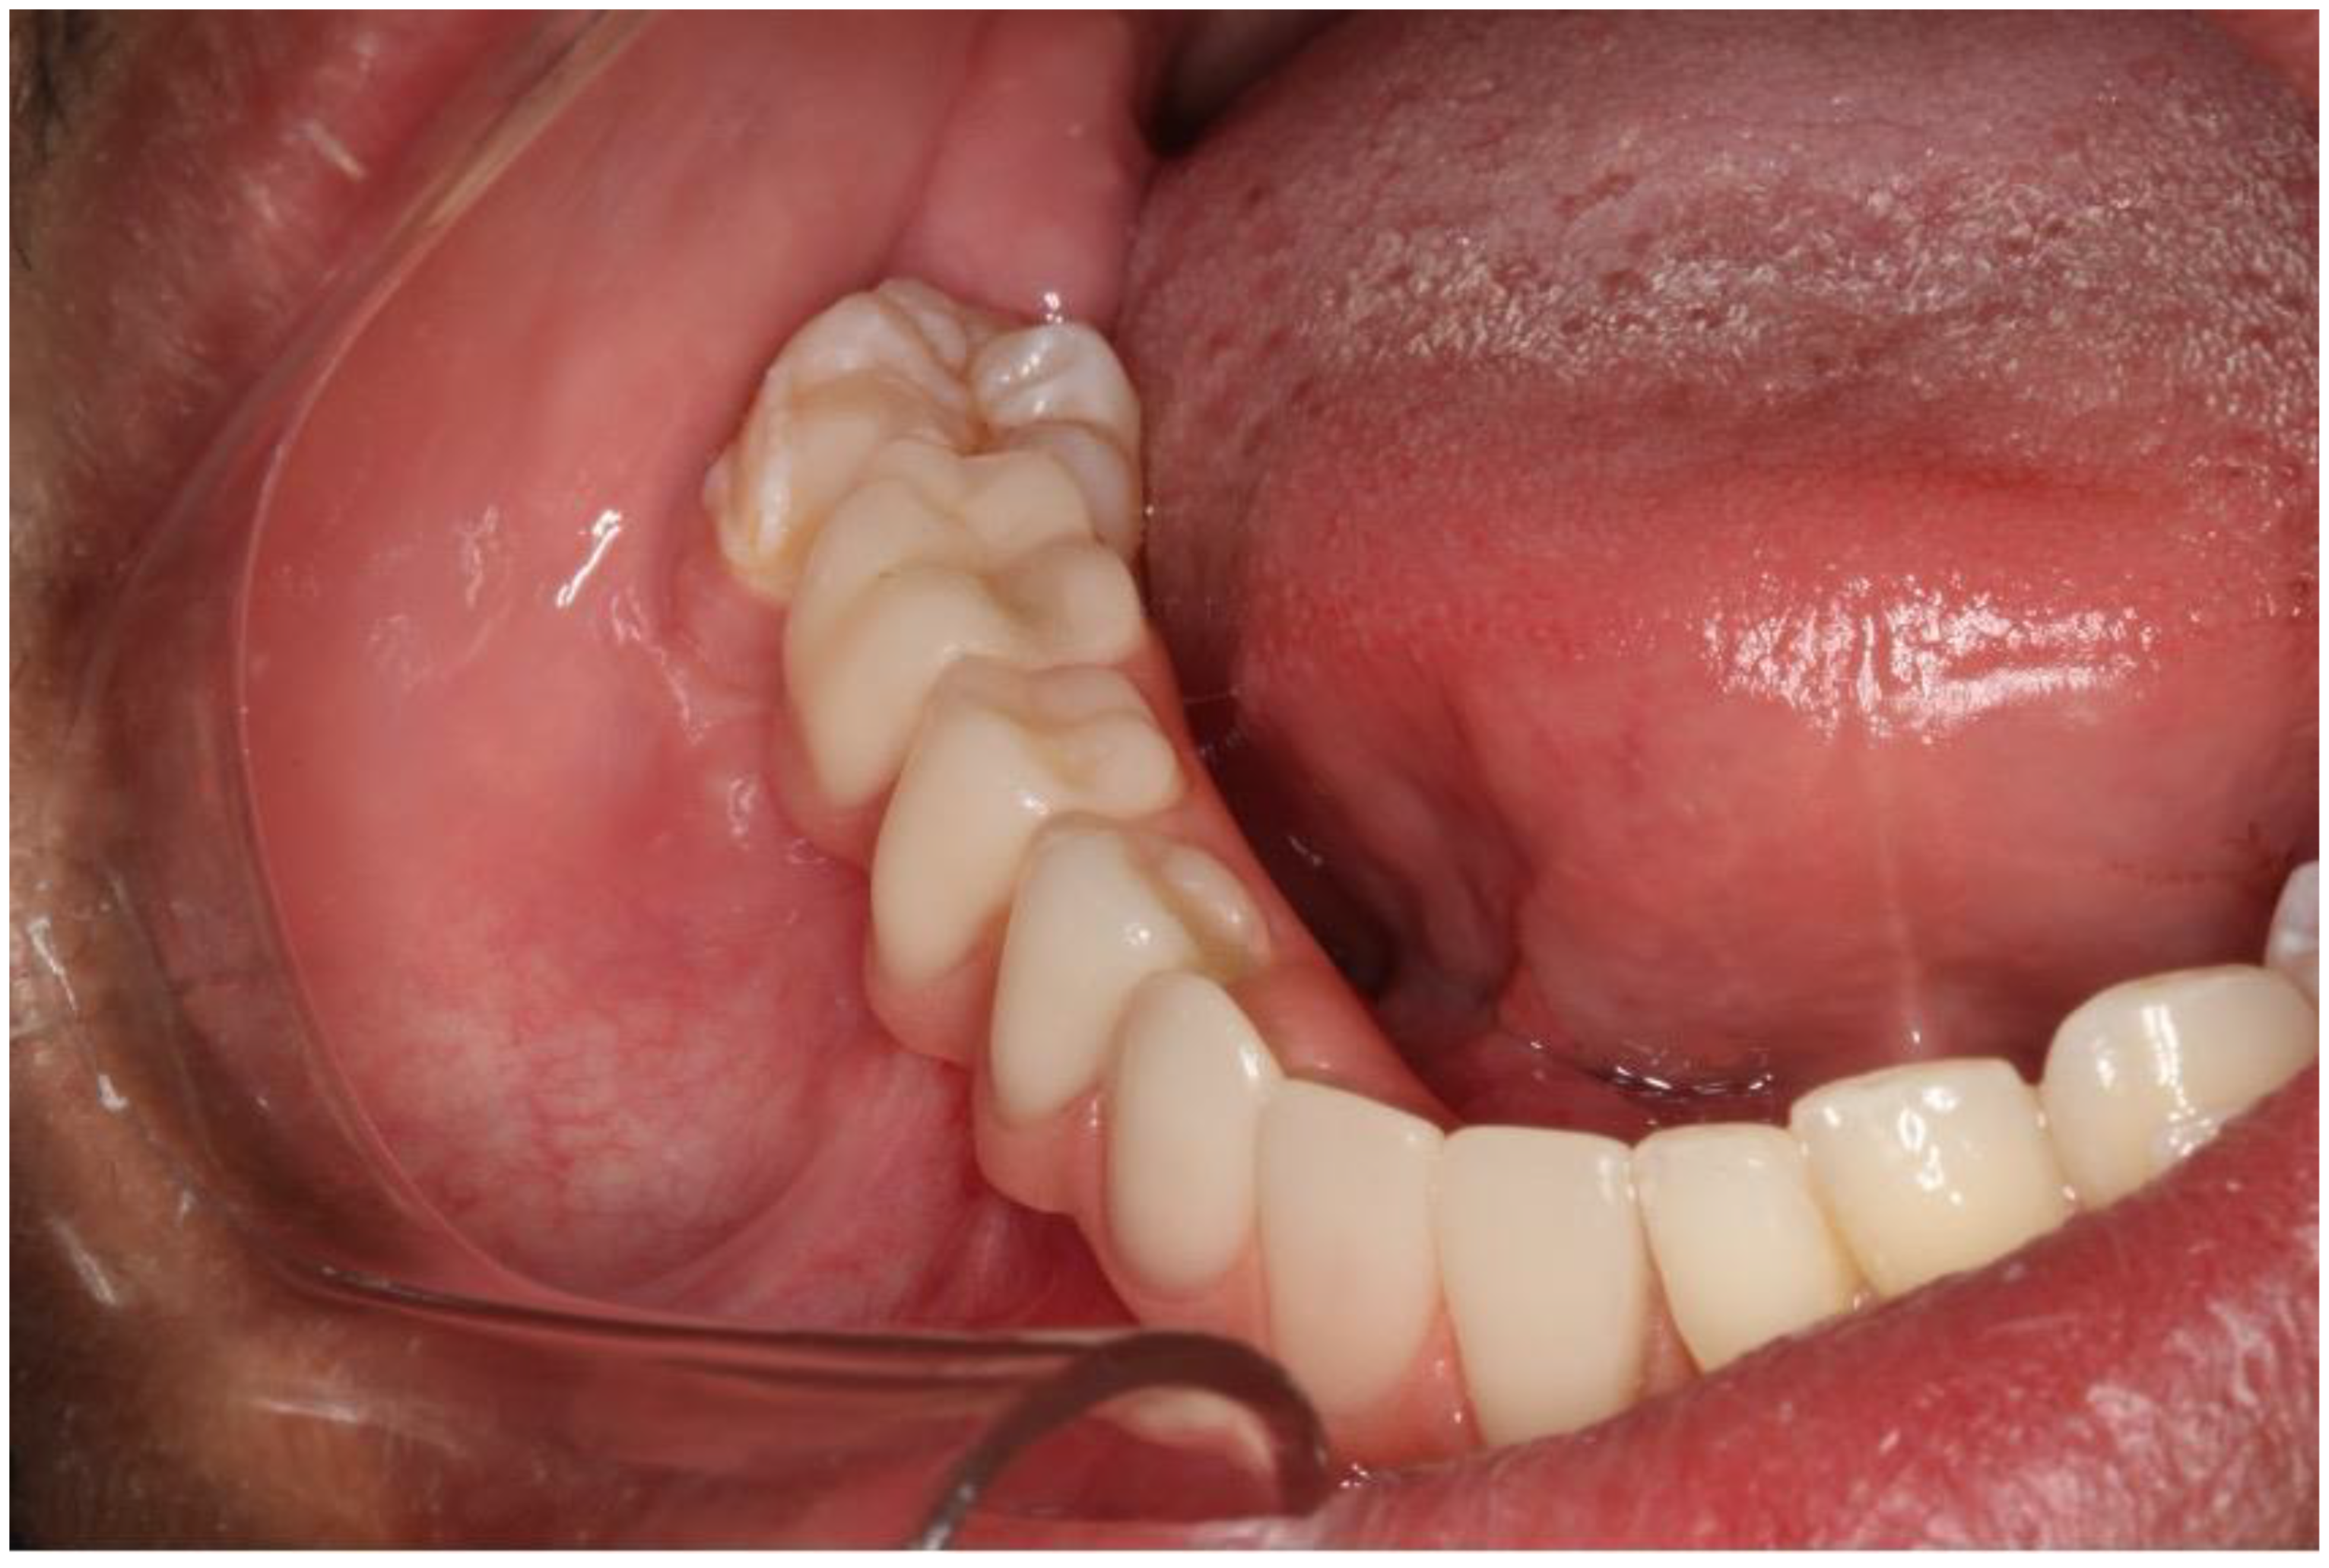

2.2. Case 2